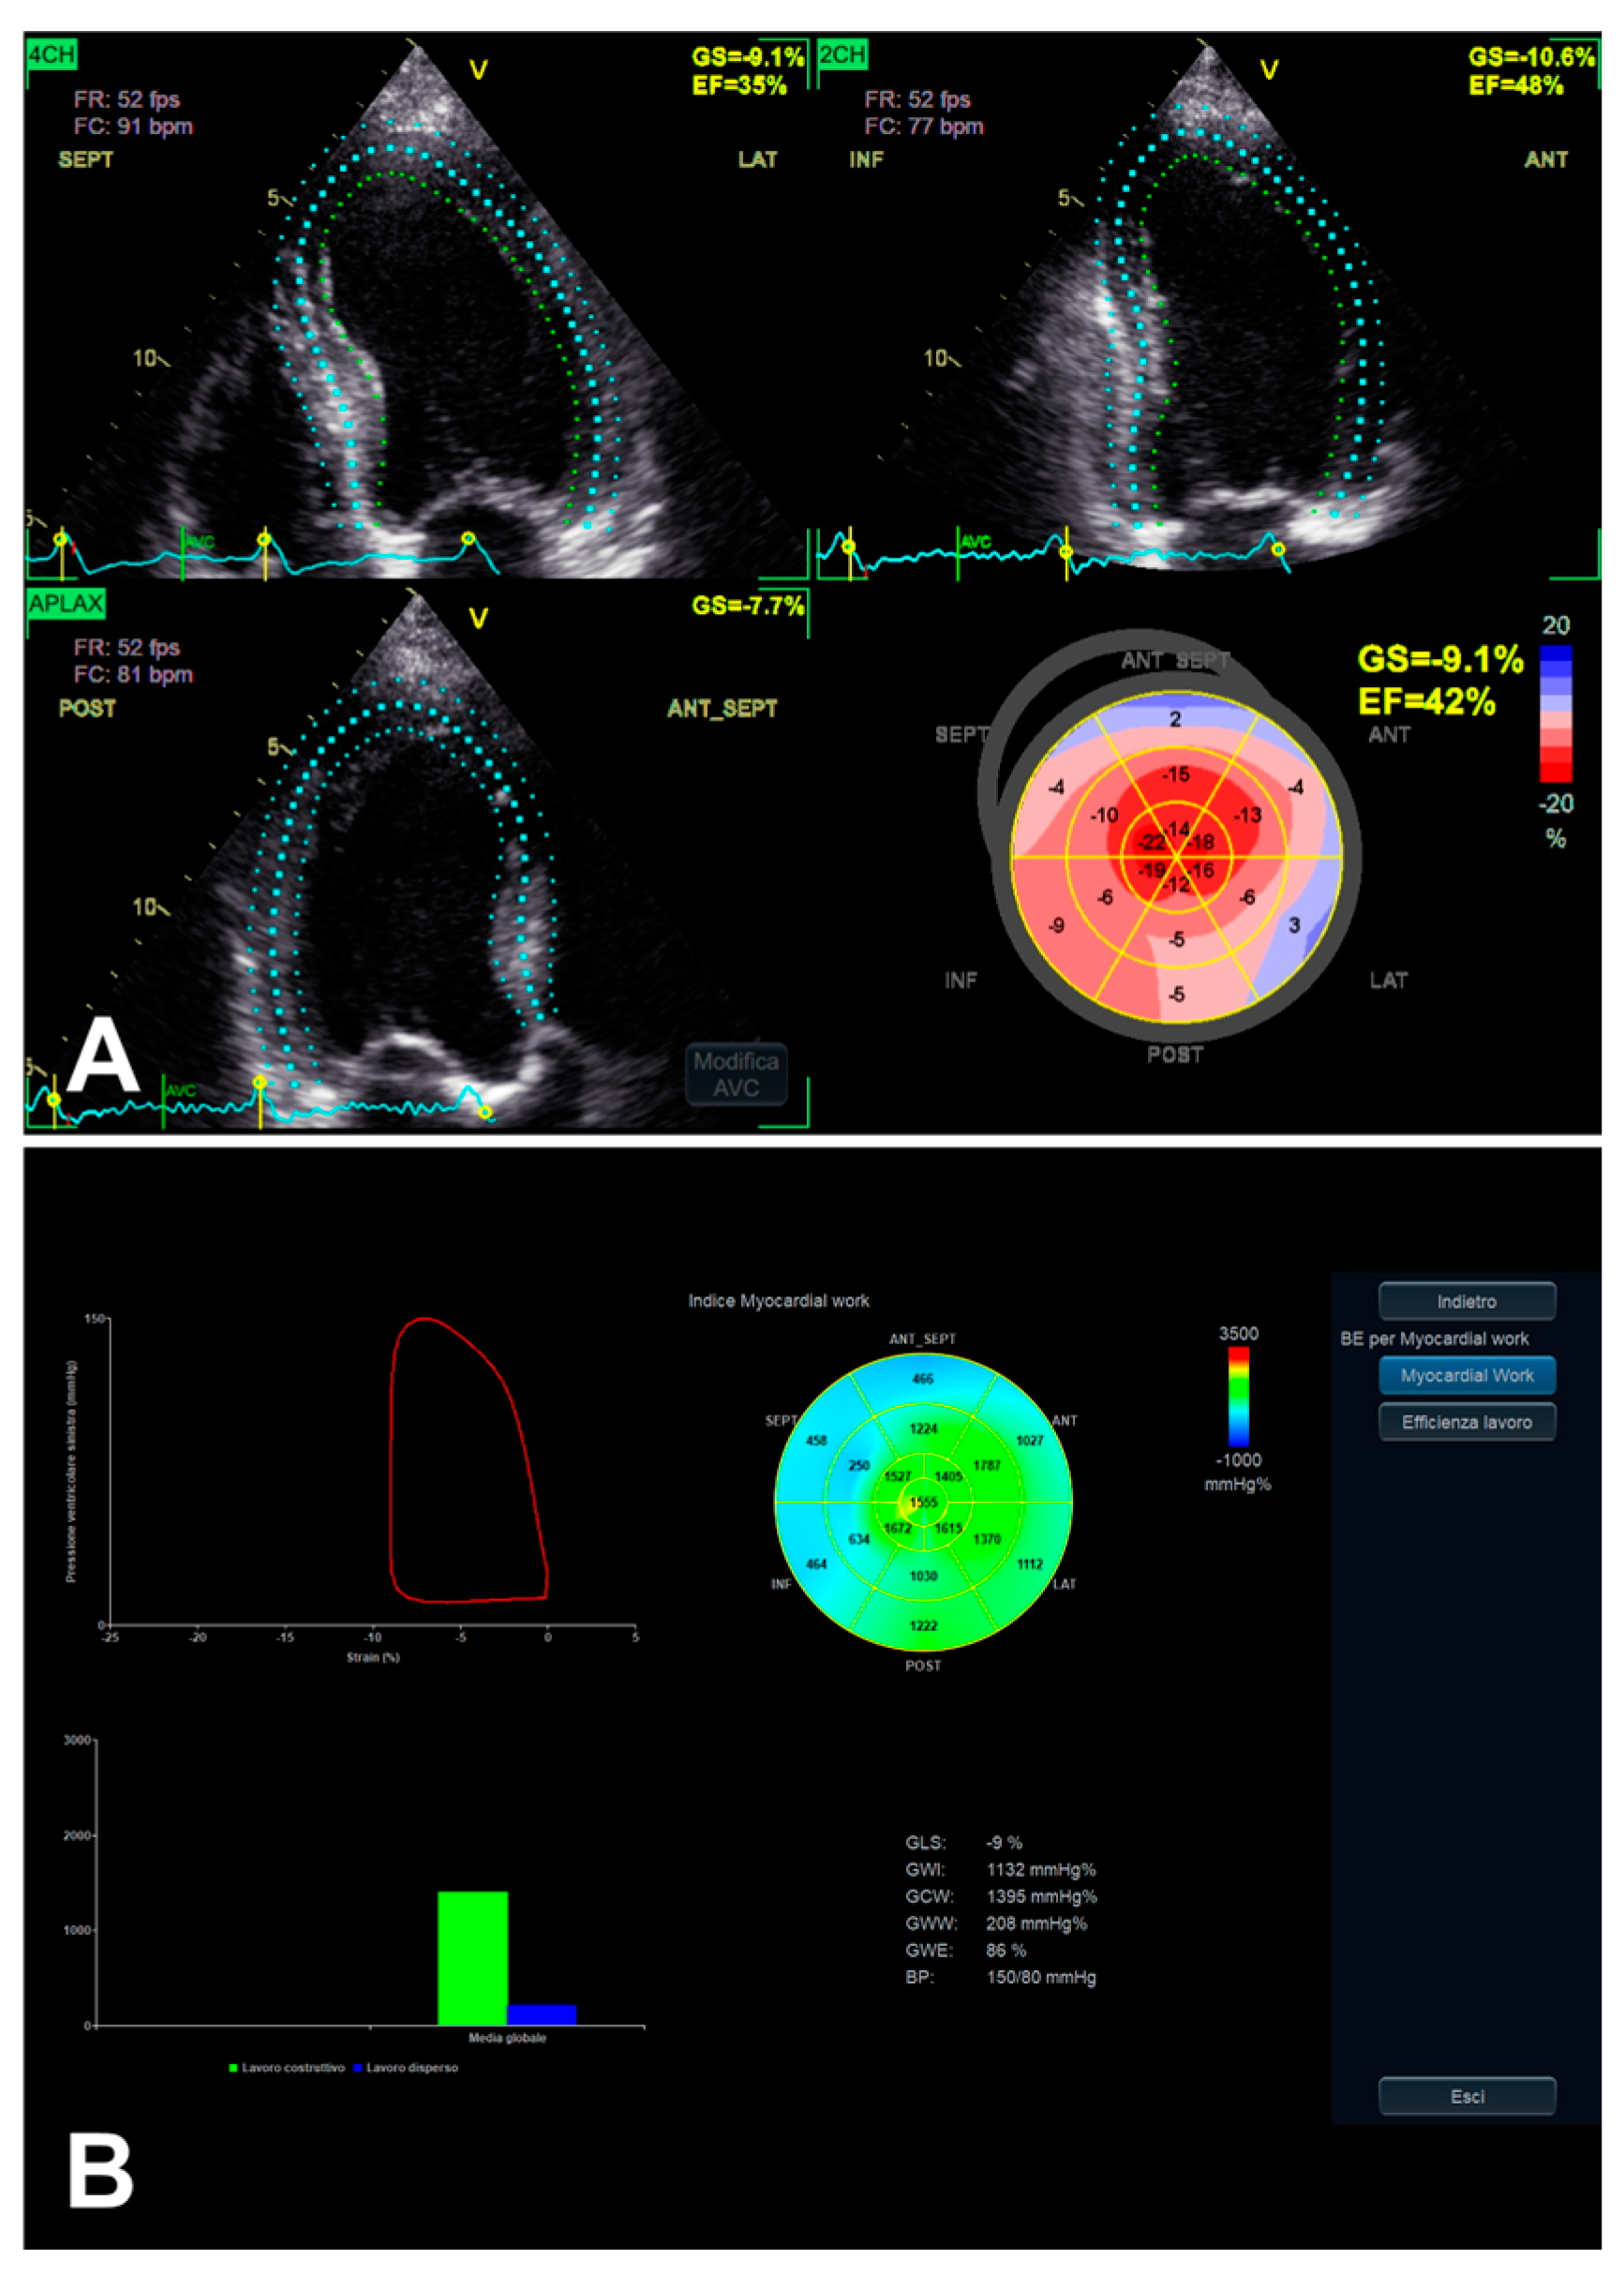

3.1. Left Ventricular Global Longitudinal Strain

3.3. Left Ventricular Myocardial Work

- Dell’Angela, L.; Nicolosi, G.L. From ejection fraction, to myocardial strain, and myocardial work in echocardiography: Clinical impact and controversies. Echocardiography 2024, 41, e15758. [Google Scholar] [CrossRef] [PubMed]

| LV GLS | 2D apical 4C, 3C, and 2C views | Probe in apical zone with 4C, 3C, and 2C views | - Prognostic/predictive value. | - Age and load dependency; - Chest shape dependency; - Image quality-related; - Intervendor and intersoftware variability. |

| LV MW | GCW | Positive work evaluated from AVO to AVC and negative work from AVC to MVO | - Relatively low intra and inter-observer variability (if good US window). | - GLS-related limits (including image quality); - AP measurement-related limits; - Single available software. |

| GWI | Total work evaluated from MVC to MVO | |||

| GWE | GCW/(GCW + GWW) | |||

| GWW | Positive work evaluated from AVO to AVC and negative work from AVC to MVO |